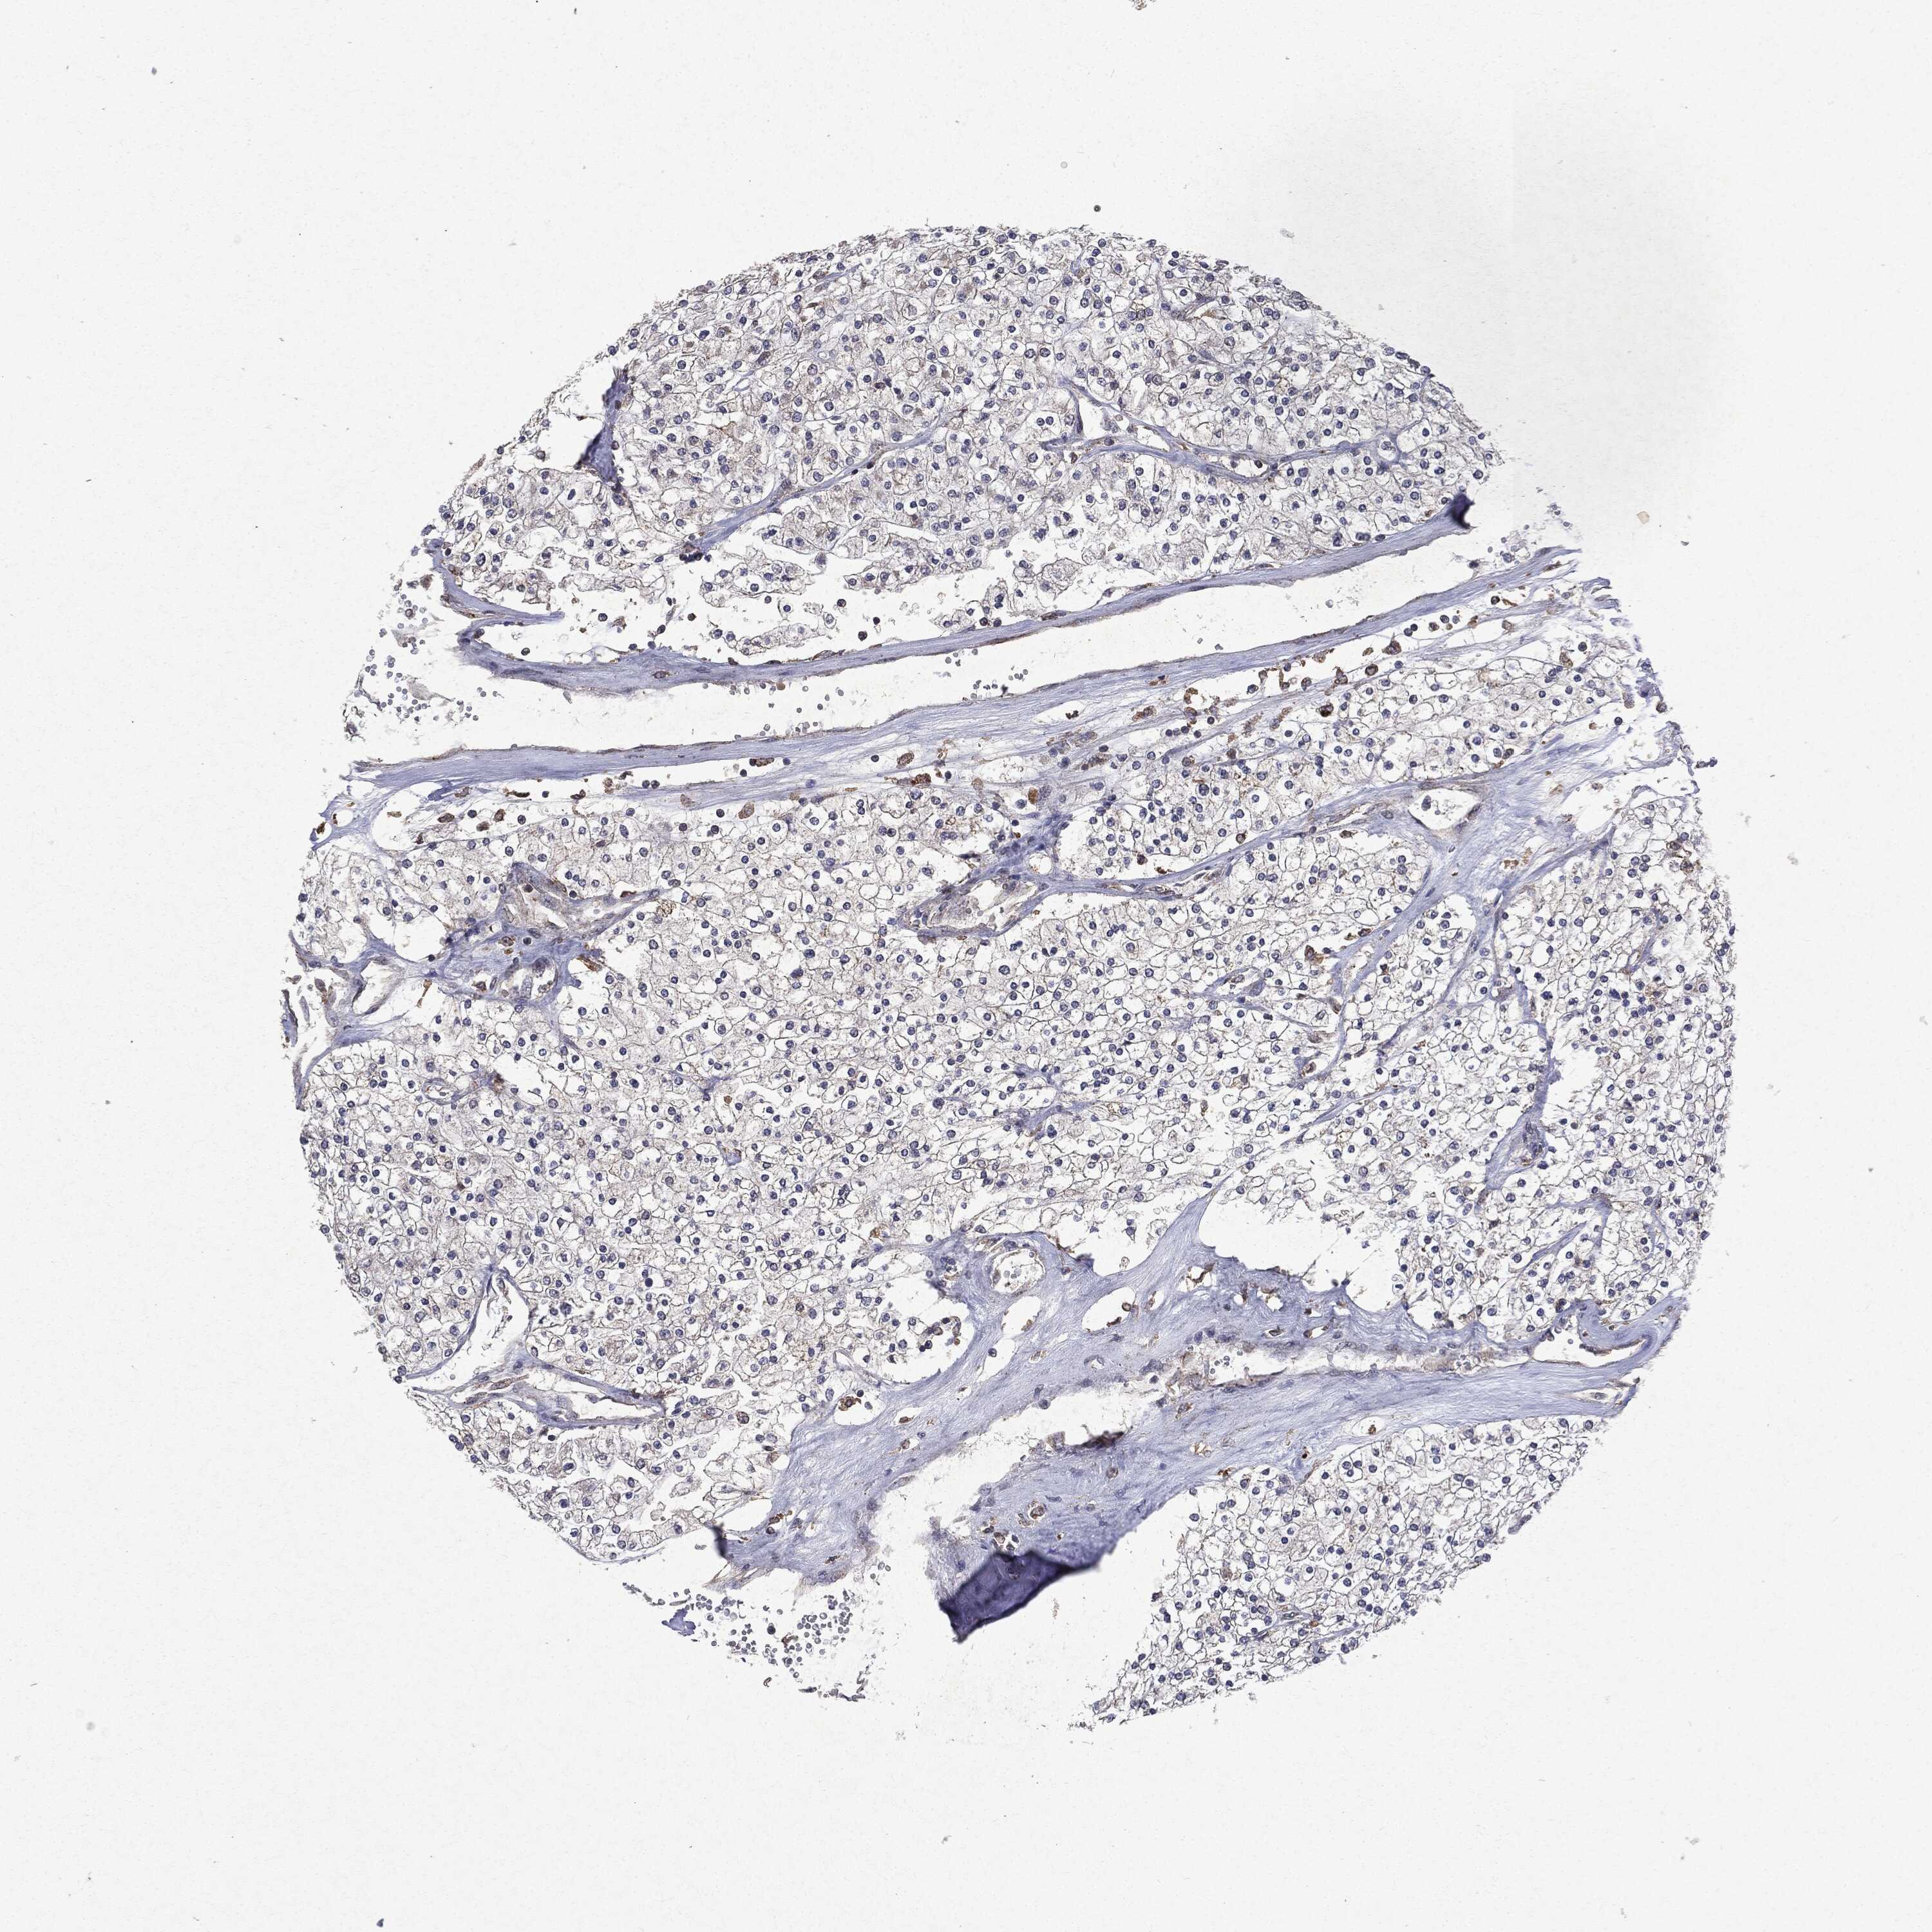

Renal cancer

Kidney chromophobe